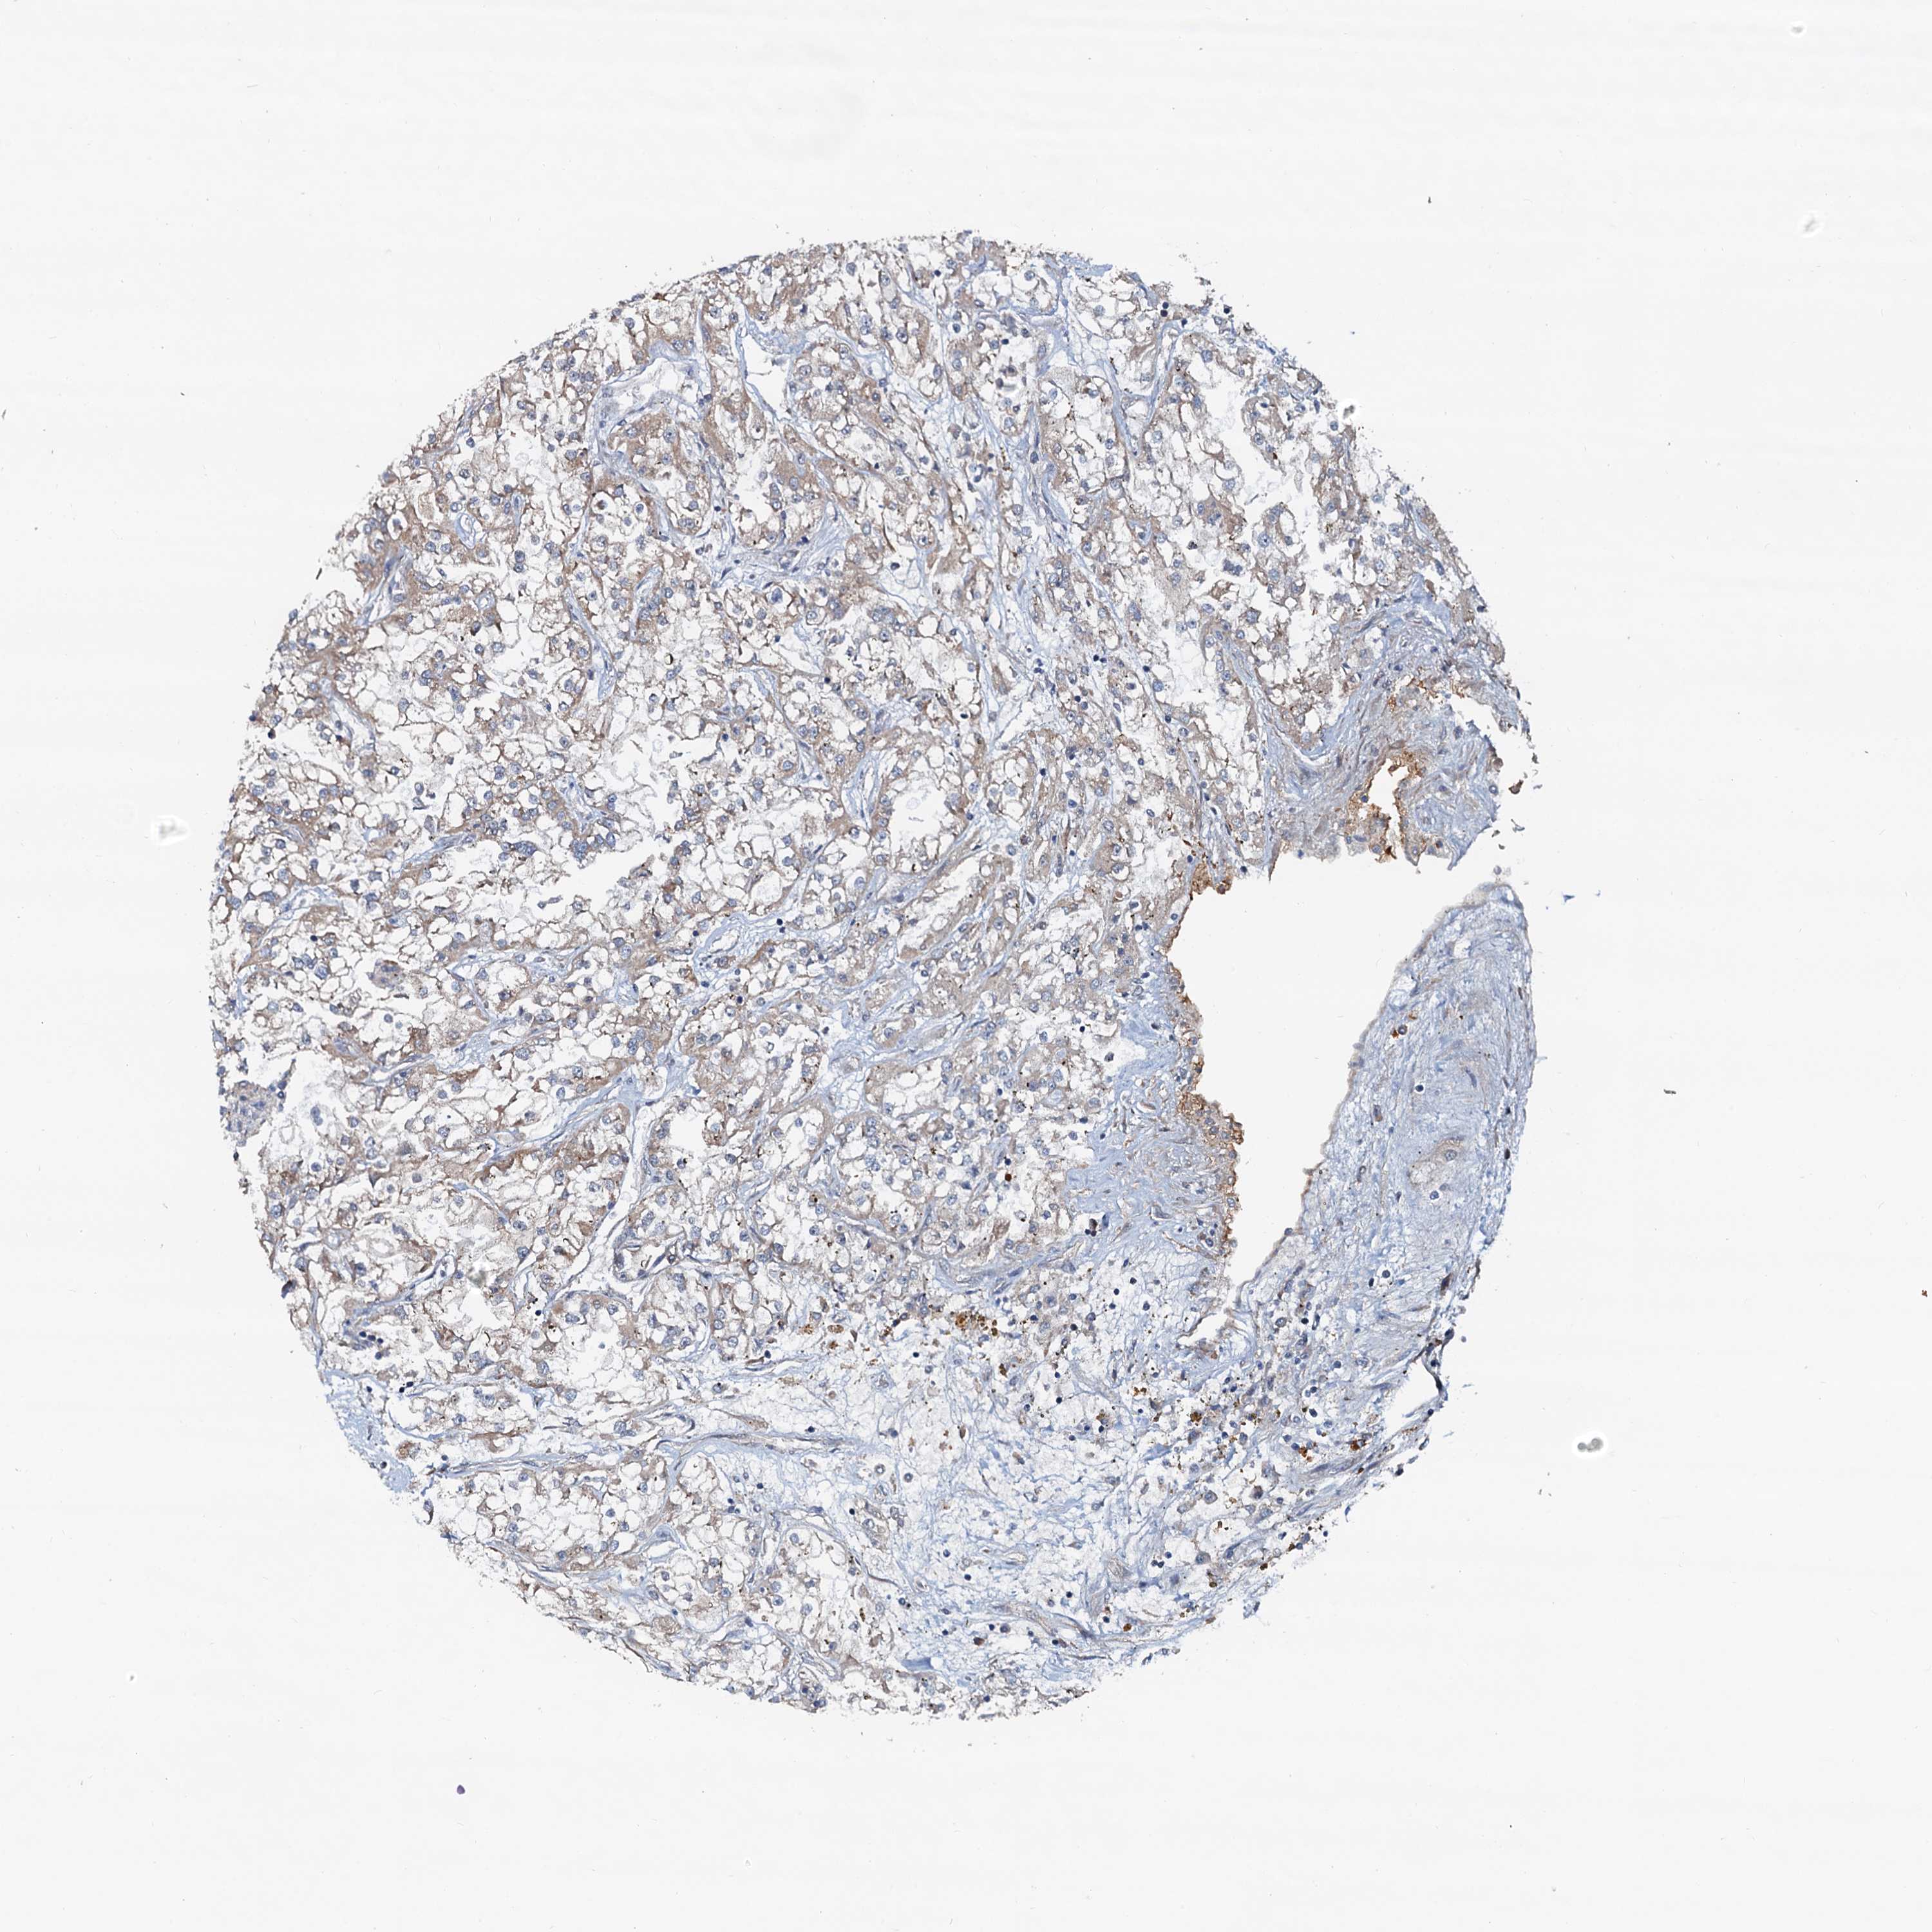

KIDNEY RENAL CLEAR CELL CARCINOMA (TCGA) - Interactive survival scatter ploti

The Survival Scatter plot shows the clinical status (i.e. dead or alive) for all individuals in the patient cohort, based on the same data that underlies the corresponding Kaplan-Meier plots. Patients that are alive at last time for follow-up are shown in blue and patients who have died during the study are shown in red.

The x-axis shows the expression levels (FPKM) of the investigated gene in the tumor tissue at the time of diagnosis. The y-axis shows the follow-up time after diagnosis (years). Both axes are complimented with kernel density curves demonstrating the data density over the axes. The top density plot shows the expression levels (FPKM) distribution among dead (red) and alive patients (blue). The right density plot shows the data density of the survived years of dead patients with high and low expression levels respectively, stratified using the cutoff indicated by the vertical dashed line through the Survival Scatter plot. This cutoff is automatically defined based on the FPKM cutoff that minimizes the p-score. The cutoff can be changed by dragging the vertical line or by entering a cutoff value in the square labeled "Current cut-off".

Under the Survival Scatter plot the p-score landscape (black curve; left axis) is shown together with dead median separation (red curve; right axis). Dead median separation is the difference in median mRNA expression between patients who have died with high and low expression, respectively. It is calculated as follows: median FPKM expression of dead patients with high expression - median FPKM expression of dead patients with low expression. This is intended to aid the user in visually exploring custom cutoffs and the associated p-scores and dead median separation.

Individual patient data is displayed and can be filtered by clicking on one or more of the category buttons on the top of the page. Categories describing expression level and patient information include: high, low, alive, dead, female, male and tumor stages. The scale of the x-axis can be toggled between linear and log-scale by clicking on the "x log" button. Mouse-over function shows TCGA ID, patient information and mRNA expression (FPKM) for each patient.

& Survival analysisi

Kaplan-Meier plots summarize results from analysis of correlation between mRNA expression level and patient survival. Patients were divided based on level of expression into one of the two groups "low" (under cut off) or "high" (over cut off). X-axis shows time for survival (years) and y-axis shows the probability of survival, where 1.0 corresponds to 100 percent.

AAGAB is potential prognostic, high expression is favorable in Kidney Renal Clear Cell Carcinoma (TCGA)

Best expression cut offi

: 9.58

P scorei

N/A

TCGA RNA samplesi

RNA-seq data is reported as average FPKM (number Fragments Per Kilobase of exon per Million reads), generated by the The Cancer Genome Atlas (TCGA) .

Normal distribution across the dataset is visualized with box plots, shown as median and 25th and 75th percentiles. Points are displayed as outliers if they are above or below 1.5 times the interquartile range. FPKM values of the individual samples are presented next to the box plot.

Average pTPM 16.3

Number of samples 521